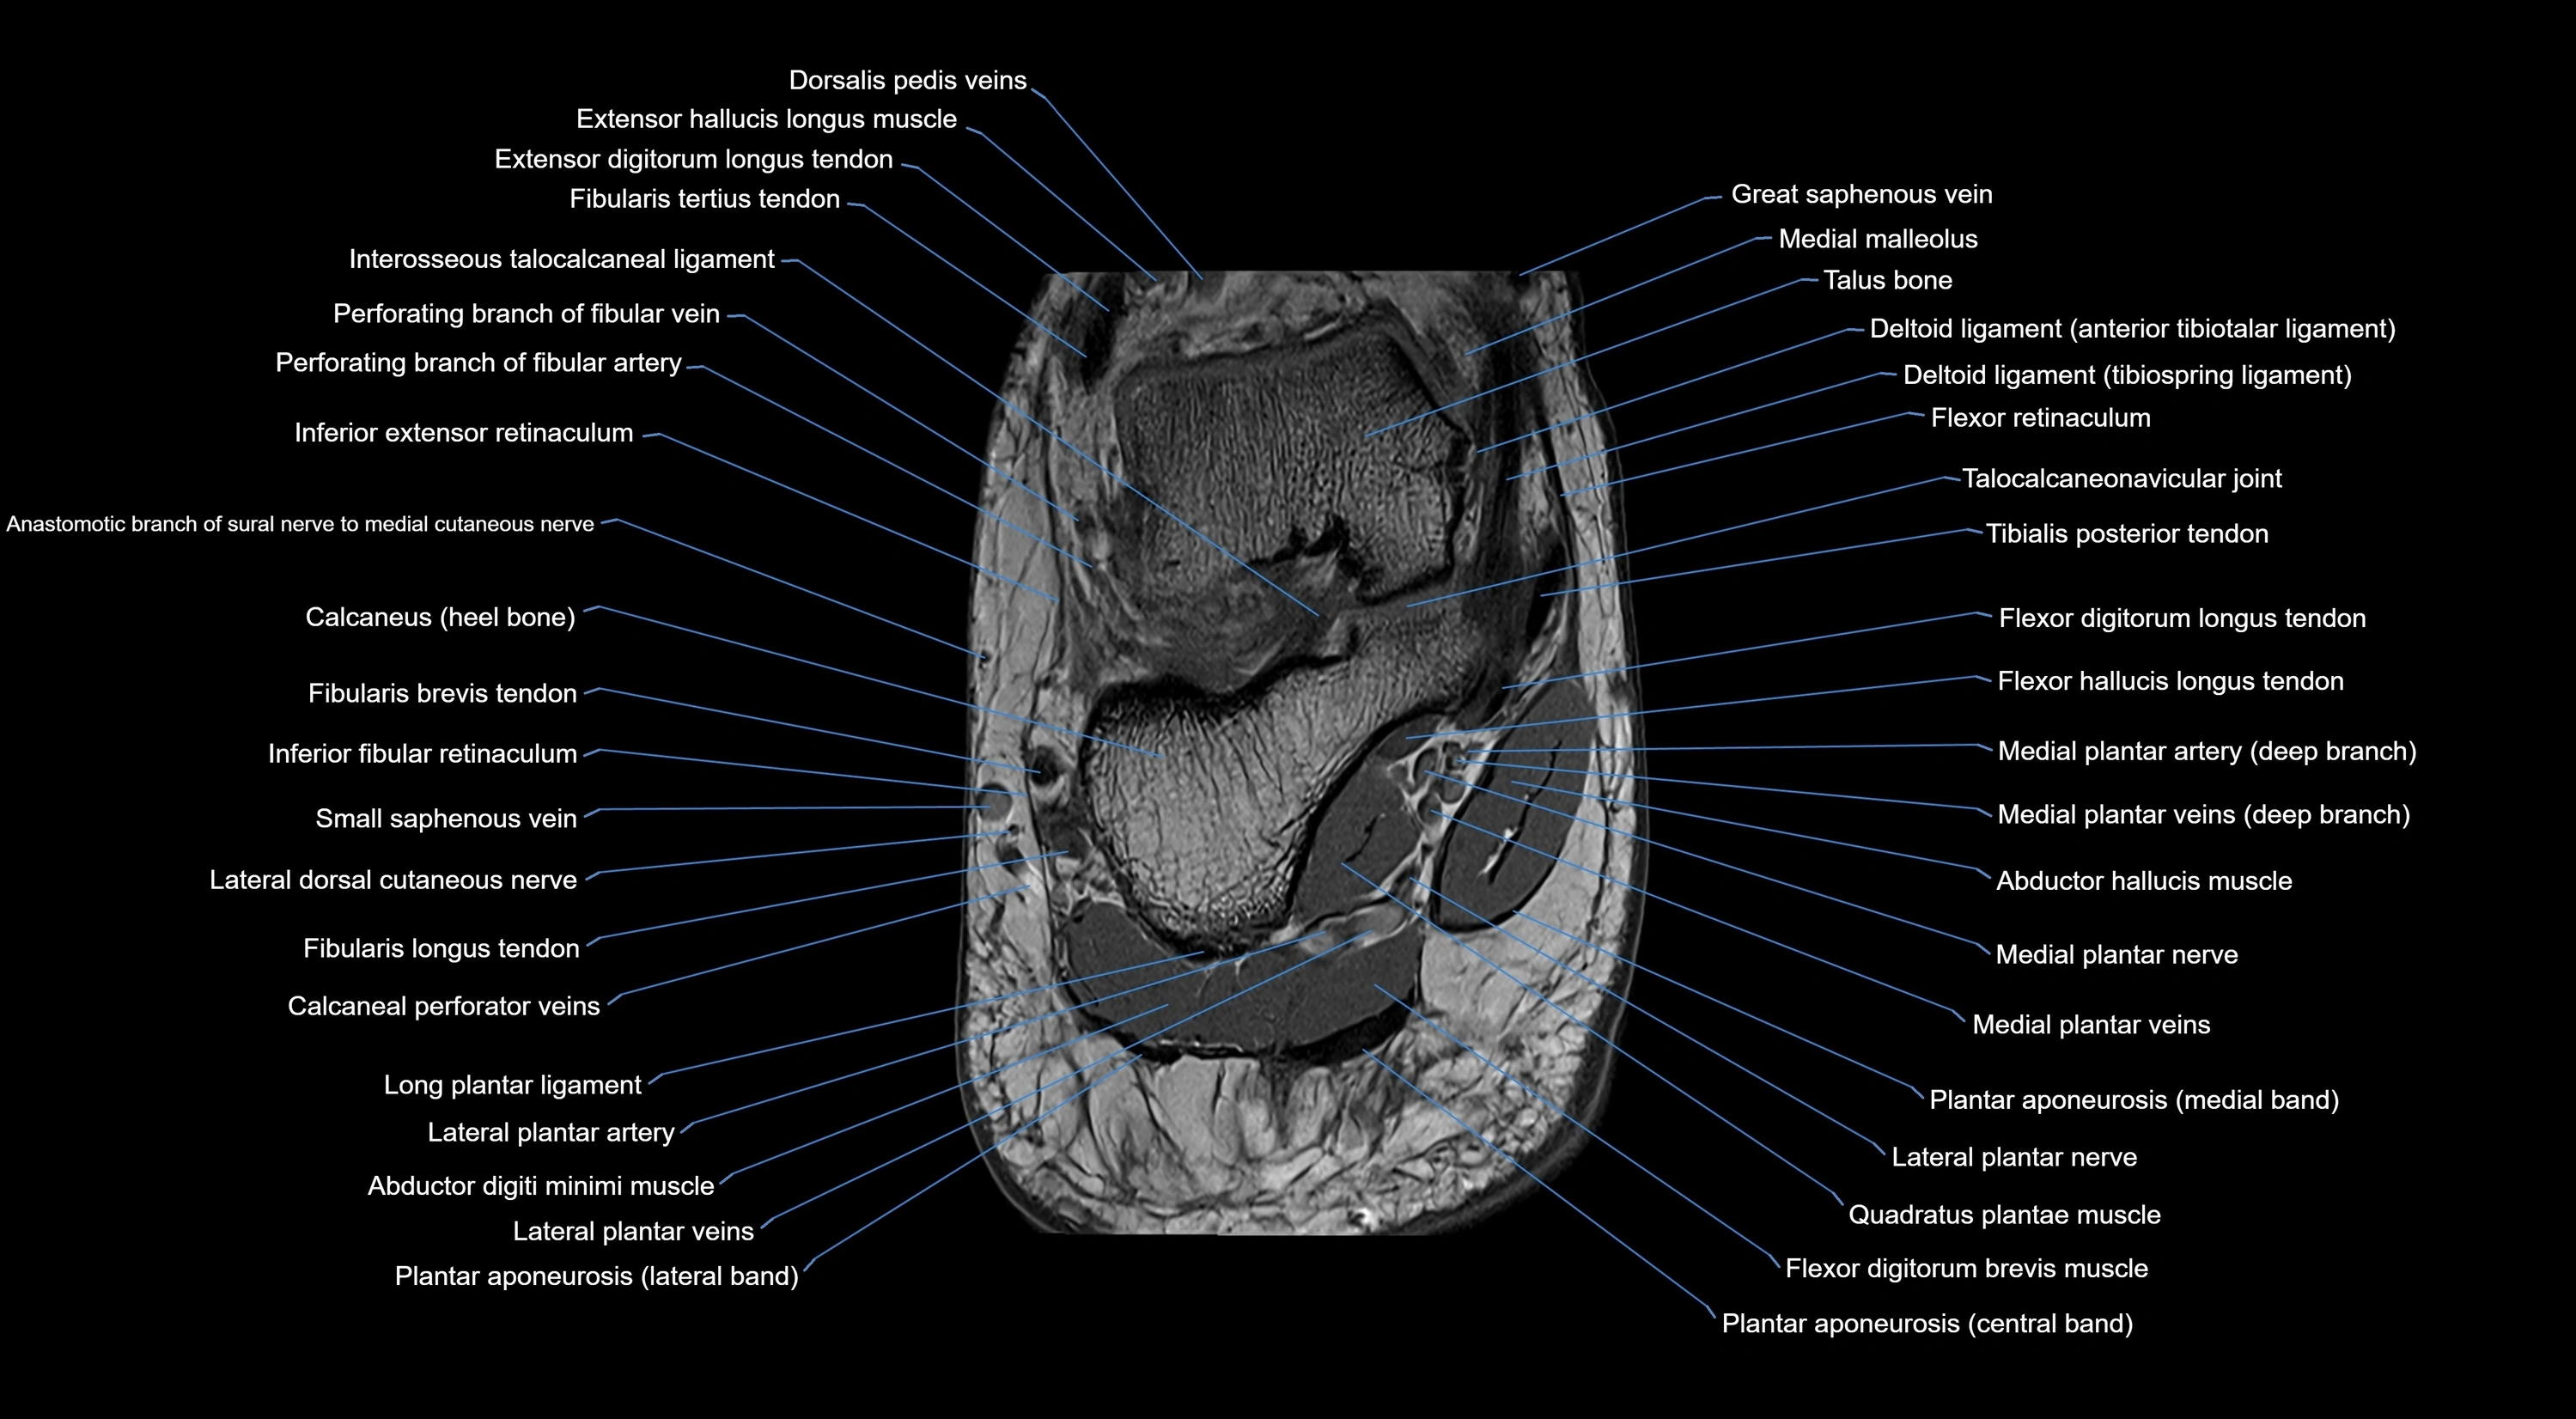

MRI image